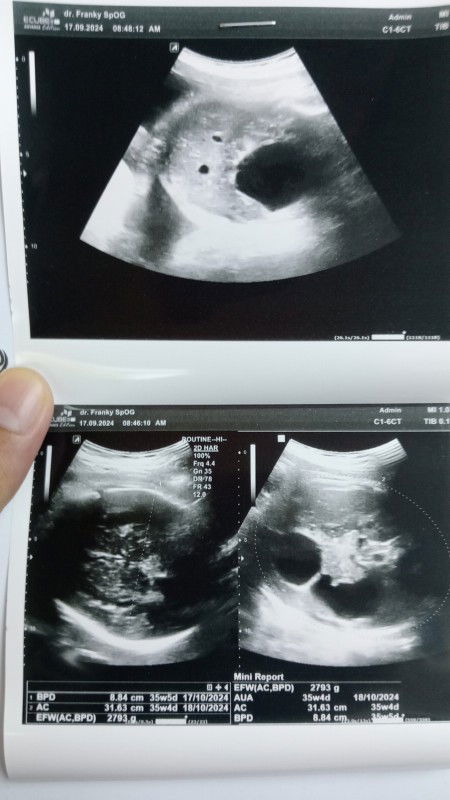

USG 37mg perbedaan sebelum dan sesudah usg

Bun, mau nanya. Di hasil USG kata dokter ada sebuah cairan diperut bayi,, dan bayi saya kecil untk ukuran 37mg 2,7g..namun kata bidan sebelum USG semuanya normal, gerak bayi juga aktif,, pertanyaannya, apa mungkin jika bayi bermasalah tidak berefek pada ibu yg sedang mengandung? Saya juga sehat2 saja tidak ada keluhan apapun

Usia kehamilan 37mg 3hr

Bun,, seberapa persenkah USG dapat dipercaya??